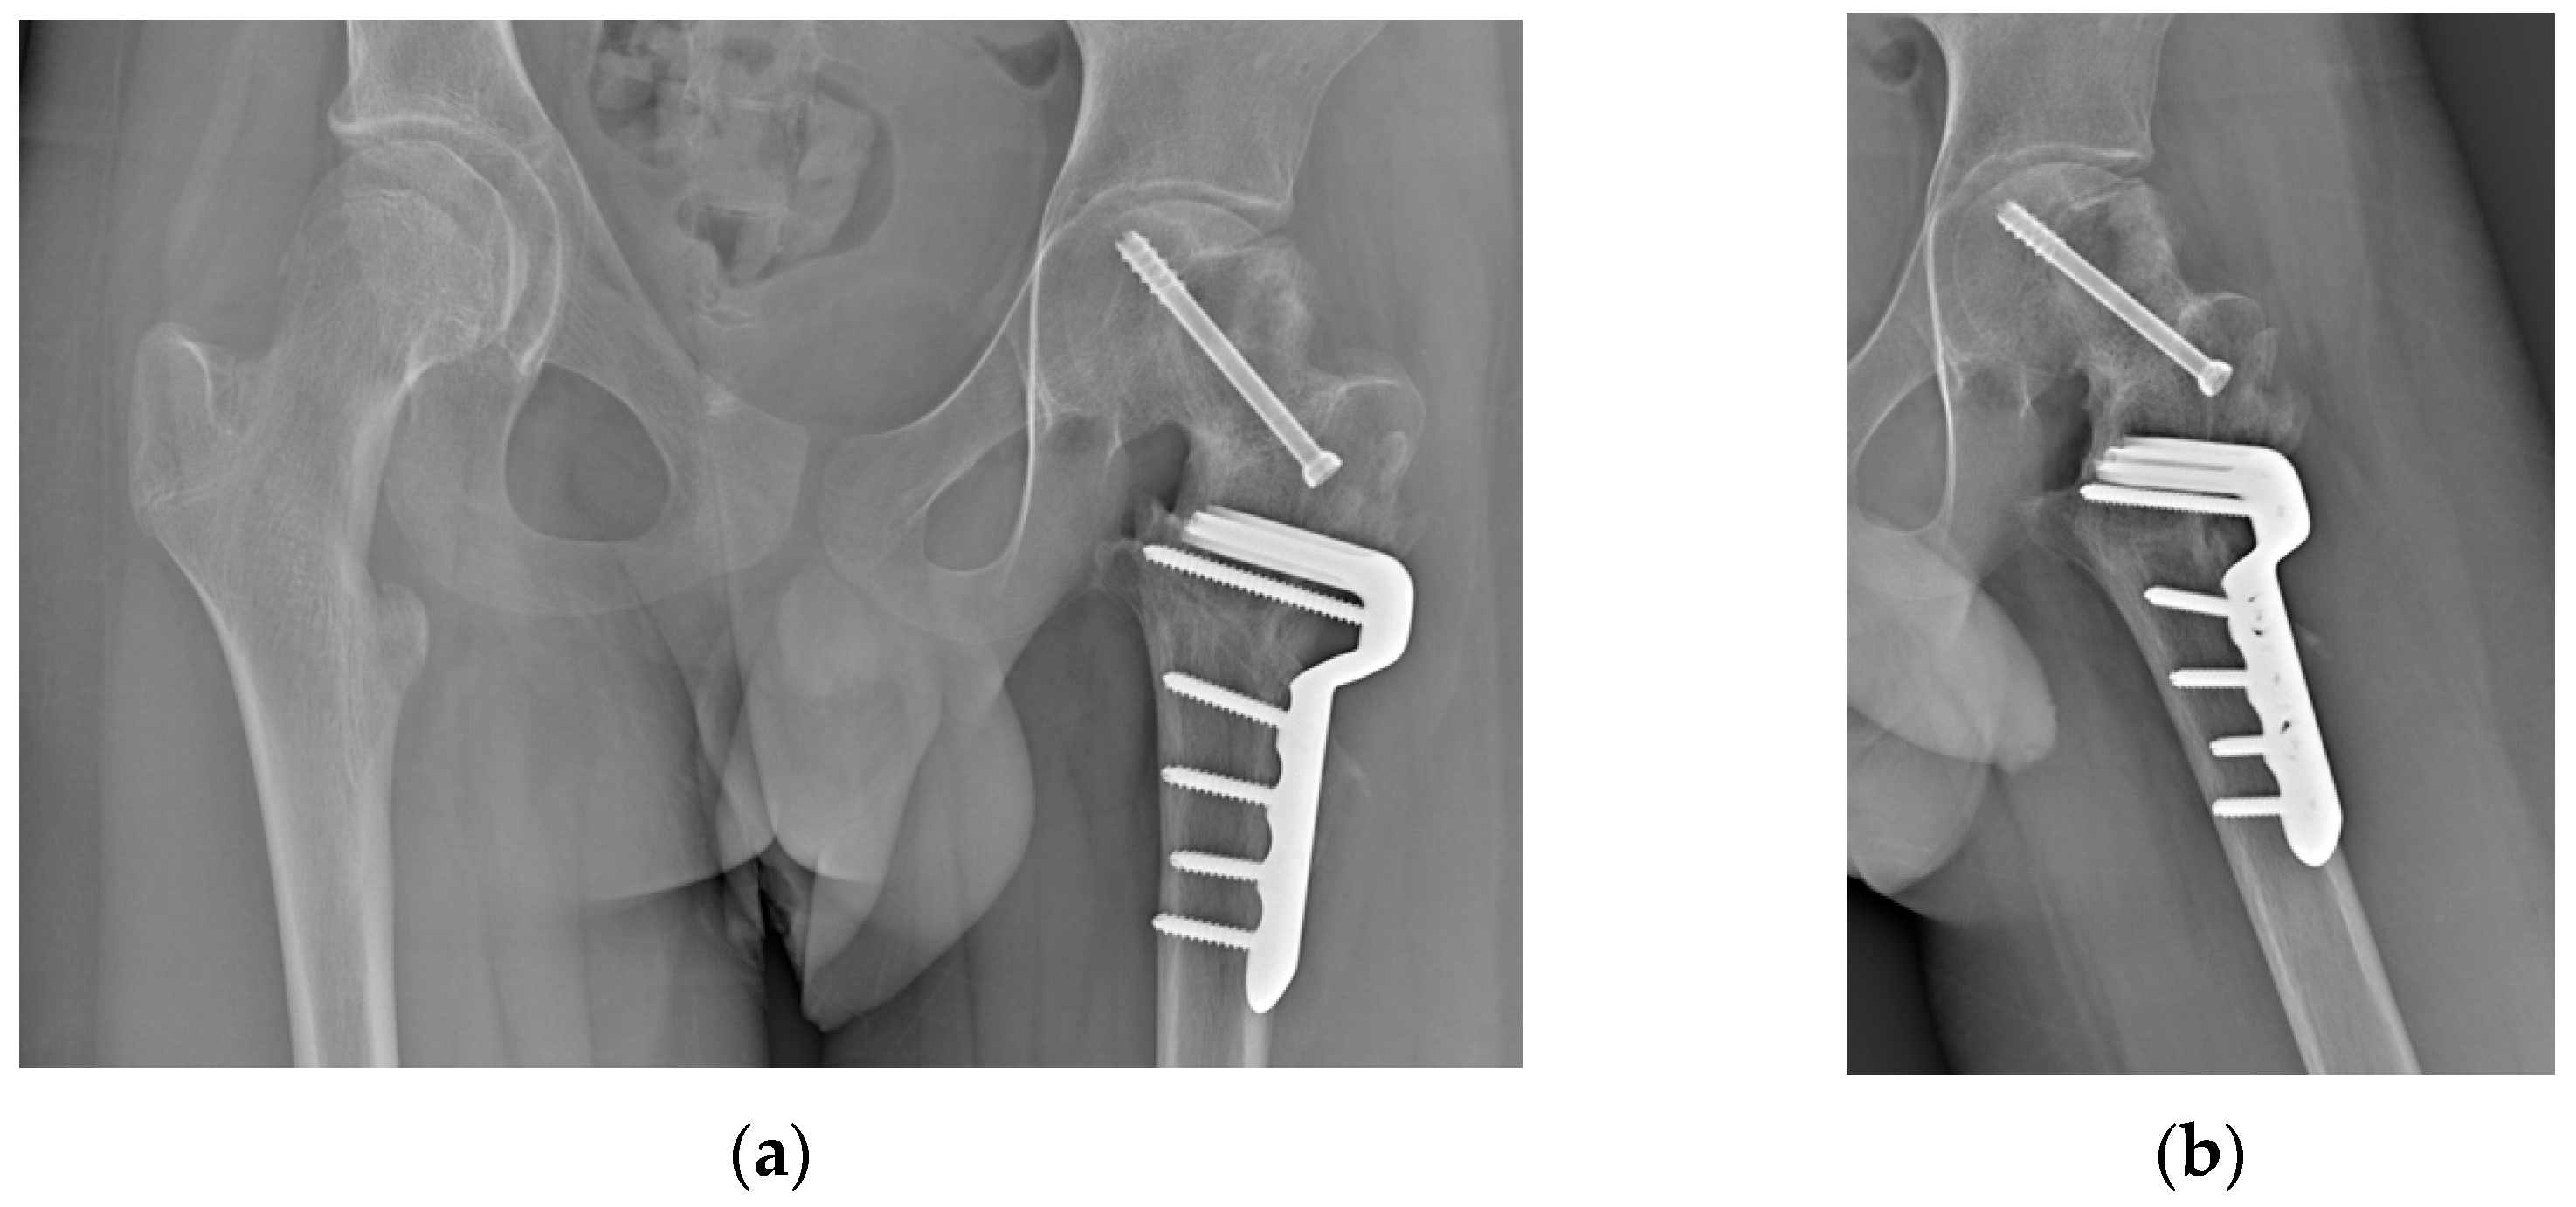

2. Case Presentation

2.2. Surgical Procedure

2.4. Results